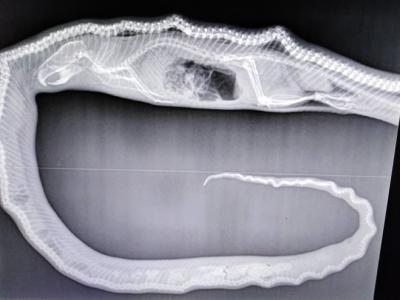

广东佛山村庄惊现35公斤重巨蟒 3名壮汉合

广东佛山村庄惊现35公斤重巨蟒 3名壮汉合力都几乎拉它不动(神...